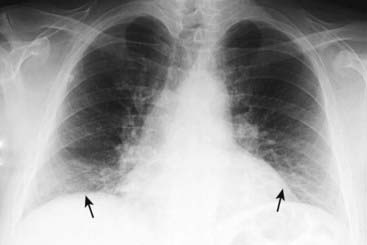

Inspiration

image A full inspiration ensures a reproducible radiograph from one time to the next and eliminates artifacts that may be confused for or obscure disease.

The degree of inspiration can be assessed by counting the number of posterior ribs visible above the diaphragm on the frontal chest radiograph.

To help in differentiating the anterior from the posterior ribs, consult Box 2-1.

If 10 posterior ribs are visible, it is an excellent inspiration (Fig. 2-12).

In many hospitalized patients, visualization of eight to nine posterior ribs is a degree of inspiration usually adequate for accurate interpretation of the image.

image Pitfall: Poor inspiration

A poor inspiratory effort will compress and crowd the lung markings, especially at the bases of the lungs near the diaphragm (Fig. 2-13). This may lead you to mistakenly think the study shows lower lobe pneumonia.

Solution: Look at the lateral chest radiograph to confirm the presence of pneumonia (see “The Lateral Chest Radiograph” in this chapter and Chapter 7).

image

Figure 2-12 Counting ribs.

The posterior ribs are numbered in this photograph. Ten posterior ribs are visible above the right hemidiaphragm, an excellent inspiration. In most hospitalized patients, eight to nine visible posterior ribs in the frontal projection is an inspiration that is adequate for accurate interpretation of the image. When counting ribs, make sure you don’t miss counting the 2nd posterior rib, which frequently overlaps the 1st rib.

Figure 2-13 Sub-optimal inspiration.

Only eight posterior ribs are visible on this frontal chest radiograph. A poor inspiration may “crowd” and therefore accentuate the lung markings at the bases (solid black arrows) and may make the heart seem larger than it actually is. The crowded lung markings may mimic the appearance of aspiration or pneumonia. A lateral chest radiograph should help in eliminating the possibility, or confirming the presence, of basilar airspace disease suspected from the frontal radiograph.